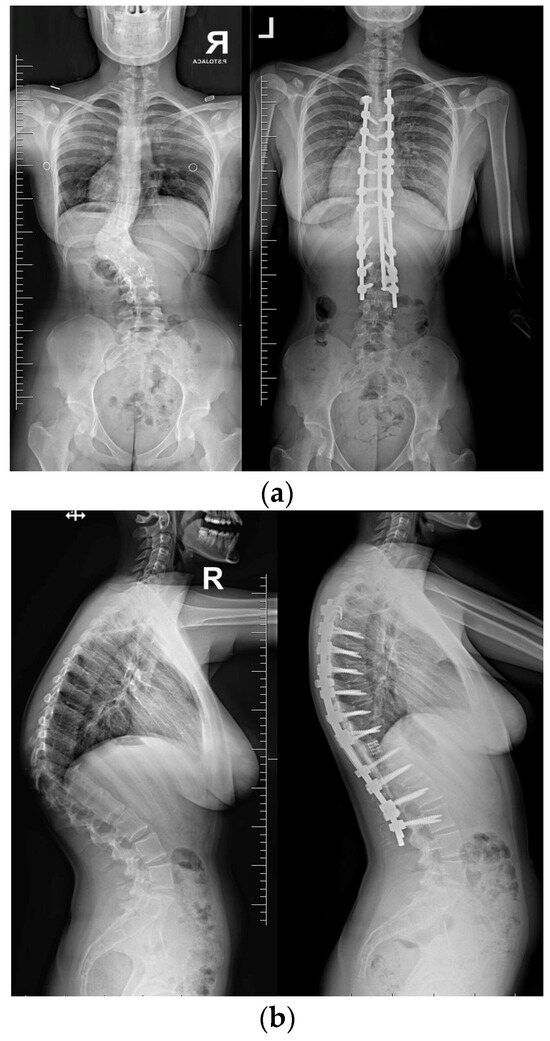

Postoperative imaging showed significant improvement in both three-dimensional planes (Figure 8).

Upon conducting a postoperative physical examination, it was observed that the patient’s shoulder symmetry and rib hump had improved significantly without any neurological or other complications. Figure 9 shows a significant improvement in the patient’s posture, sagittal balance (focal thoracic kyphosis from 108° to 43°), and coronal balance (from 63° to 25°). The patient was discharged 5 days after surgery; no brace was ordered. Figure 10 and Figure 11 show the X-rays and 3D-CT of the patient at the final follow-up.

Figure 8. Standard standing AP (a) and lateral (b) X-rays of the 16-year-old female after undergoing surgical treatment. These X-rays were performed just after surgery.